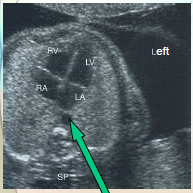

where is the apex?

on the anterior surface pointing slightly to the rt

there is rib shadow on th elt